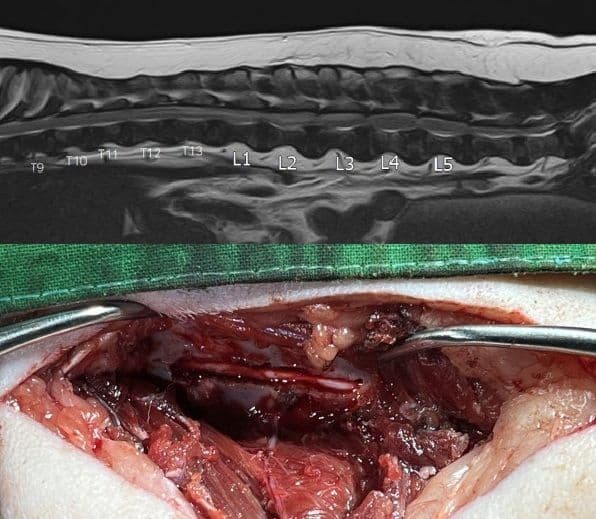

또한 정형외과 질환이 아닌 신경학적인 문제로 불편함을 겪는 환자의 경우, 신경의 회복을 위해 신속한 진단과 수술로의 연계가 중요합니다. 뼈와 근육의 정렬뿐 아니라 그 사이를 흐르는 신경의 흐름까지 완벽하게 이해하여 고난이도 신경외과 수술을 진행하고 있습니다.

신경외과 수술

Neurosurgery Center

디스크 수술

Hemilaminectomy, Ventral slot